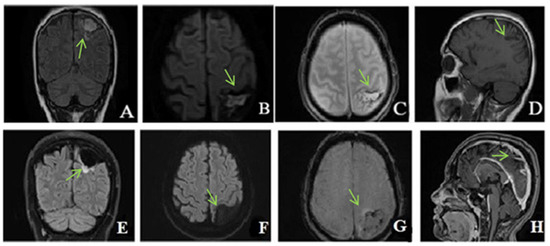

Figure 6. MRI without contrast enhancement ((A)—T2 axial, (B)—FLAIR coronal, (C)—DWI axial, (D)—ADC axial, (E)—venous TOF sagittal) shows hyperintensities of the thalamic nuclei on T2, FLAIR and DWI, with areas of restricted diffusion included and no flow in Galen’s vein, internal cerebral veins, straight sinus, and inferior sagittal sinus.

MRI showed (Figure 6) changes evoking venous thrombosis of left transverse and sigmoid sinuses, straight sinus, vein of Galen, internal cerebral and basal veins with extensive venous infarcts at the level of bilateral basal ganglia and a left temporo-occipital subcortical area.

She was admitted to the intensive care unit for continuous monitoring and started receiving anticoagulant and supportive treatment represented by continuous intravenous unfractionated heparin with flow adapted to the APTT value, isotonic fluids, vitamin therapy, physical therapy, pneumatic compression, and empiric antiviral therapy until encephalitis was excluded.

On the first day after admission, the patient′s clinical condition deteriorated. She became febrile, presented episodes of drowsiness alternating with spontaneous wakefulness and psychomotor agitation, involuntary hyperextension movements at the thoracic level, bilateral grasping, and plantar clonus bilaterally, and she was only reacting to nociceptive stimuli. The ophthalmological examination ruled out papilledema. A lumbar puncture was performed, and the result was negative for bacteria and viruses. The thrombophilia profile tests were requested and were found to be positive for: homozygous V H129 R mutation, heterozygous PAI1 4G/5G, and homozygous MTHFR A 1289C mutation.

In the following days, the patient′s condition continued to worsen. She did not respond to nociceptive stimuli, spontaneously mobilized her limbs, and had involuntary movements of the jaw. Considering the unfavorable and unpredictable evolution, in agreement with the family, we decided to perform therapeutic abortion. A new brain CT was performed (Figure 7).